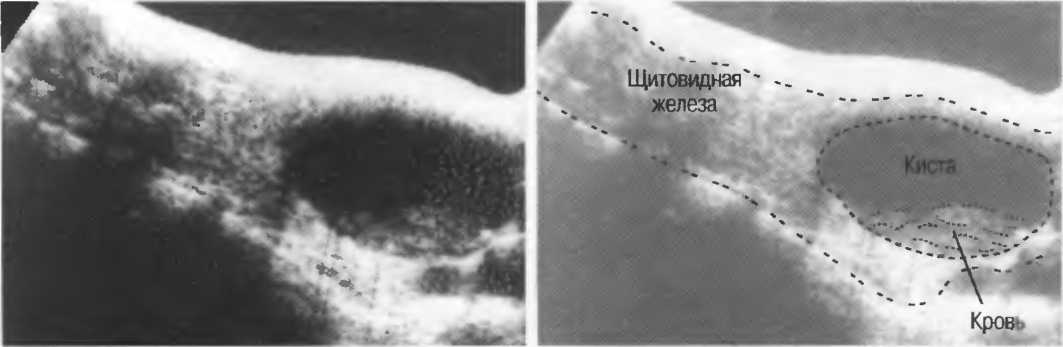

Кисты

Киста, как правило, визуализируется в виде анэхогенной зоны, при этом структуры, расположенные за кистой, обычно усилены: полость кисты анэхогенна, поскольку в ней нет структур с различным акустическим сопротивлением. В результате того что жидкость не поглощает ультразвук в такой же степени, что и ткань, эхо-сигналы от расположенных позади кисты структур гиперкомпенсированы сканером и выглядят усиленными — появляется эффект усиления задней стенки (рис. 14а,б).

Киста определяется в виде анэхогенной зоны с усилением по задней стенке. Если в кисте есть внутренние зхоструктуры, то они могут быть реальными или являться артефактами.

Артефакты могут определяться в любой кистозной структуре (такой, например, как мочевой пузырь или желчный пузырь) и чаще определяются ближе кпереди, становясь менее выраженными на глубине. Они исчезают или меняют свой характер при изменении положения датчика. Но истинные структуры в кисте, такие как перегородки, сохраняют свое местоположение независимо от положения датчика. Истинные отражения имеют место при наличии сгустка крови, гноя, некротической взвеси, и все это чаще визуализируется по задней стенке: если эти структуры не фиксированы к стенке, они изменяют свое положение при перемене положения тела пациента (рис. 16).

Осадок в кисте может флотировать, формируя уровень, изменяющий свое положение при перемещении пациента (рис. 16б,в).